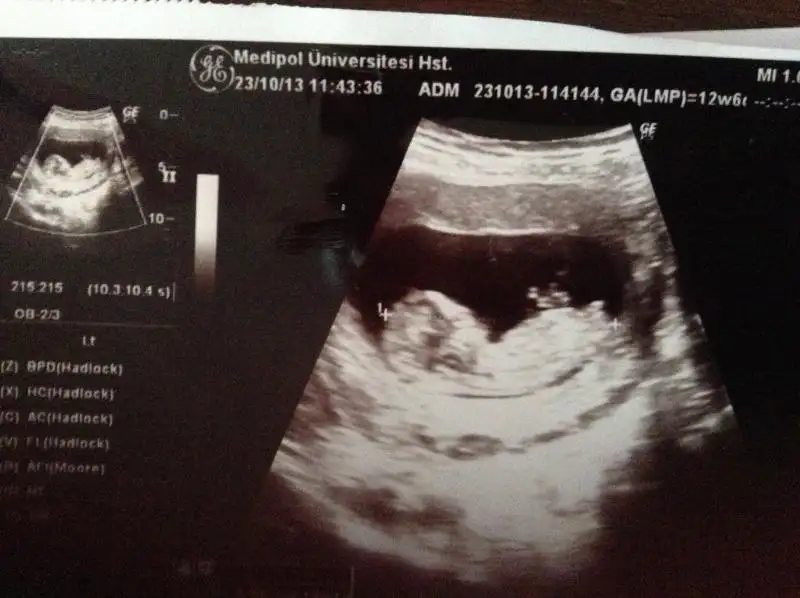

Benimkine de bakar mısınız 12+1 burada

çok merak ediyoruz

Eklenmiş Resmin önizlemesiEki Görüntüle 867747